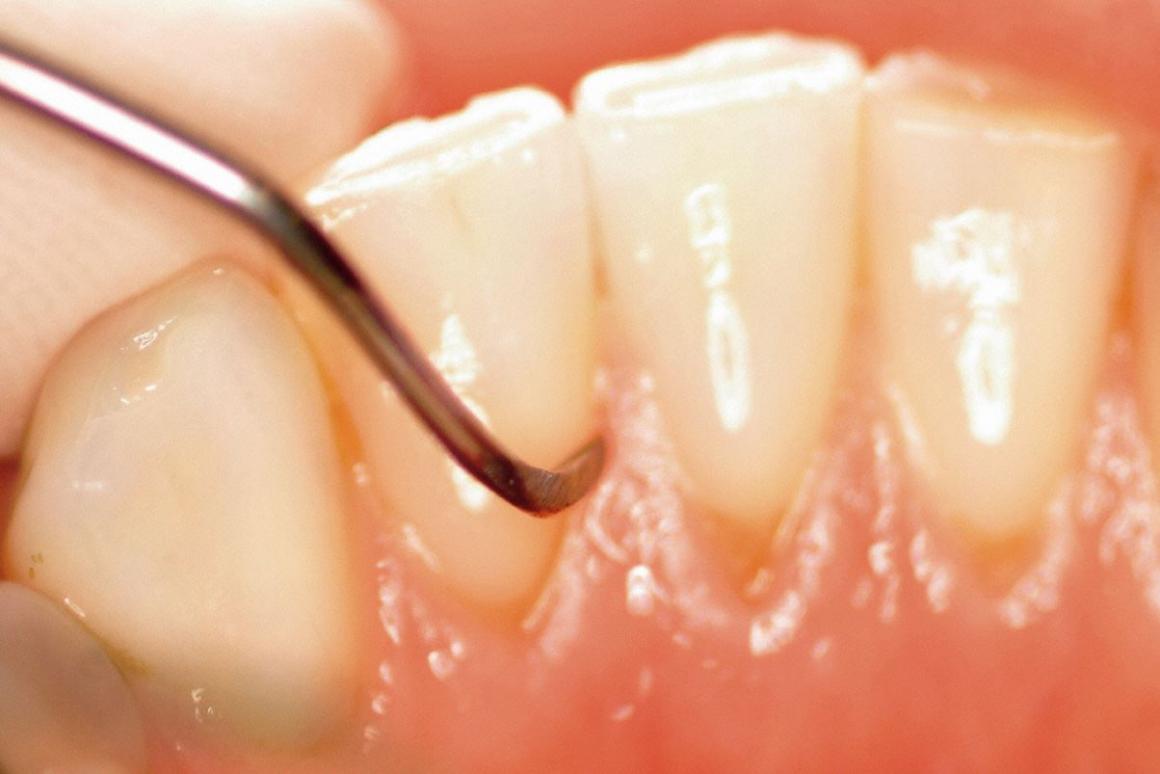

Vor Beginn einer Parodontalbehandlung ist eine Befunderhebung des Zahnhalteapparates (Parodontium) nötig. Da die radiologische Bewertung eher einen überprüfenden Charakter hat, sind die Sondierungswerte und die Beurteilung des Parodontiums sichere Parameter für die Diagnostik.

Die Zahnfleischtaschen werden gemessen, die Blutung wird beobachtet. Bei Code 3 und Code 4 wird eine Parodontalbehandlung notwendig.

Die geschlossene Kürettage ist die Standard-Therapie der Parodontitis, die ohne operativen Eingriff verläuft.

Sie beinhaltet die intensive Reinigung der Wurzeloberflächen von Bakterien und festen Belägen sowie das Glätten der Wurzeloberflächen unter Einsatz von Hand- und Ultraschallinstrumenten.